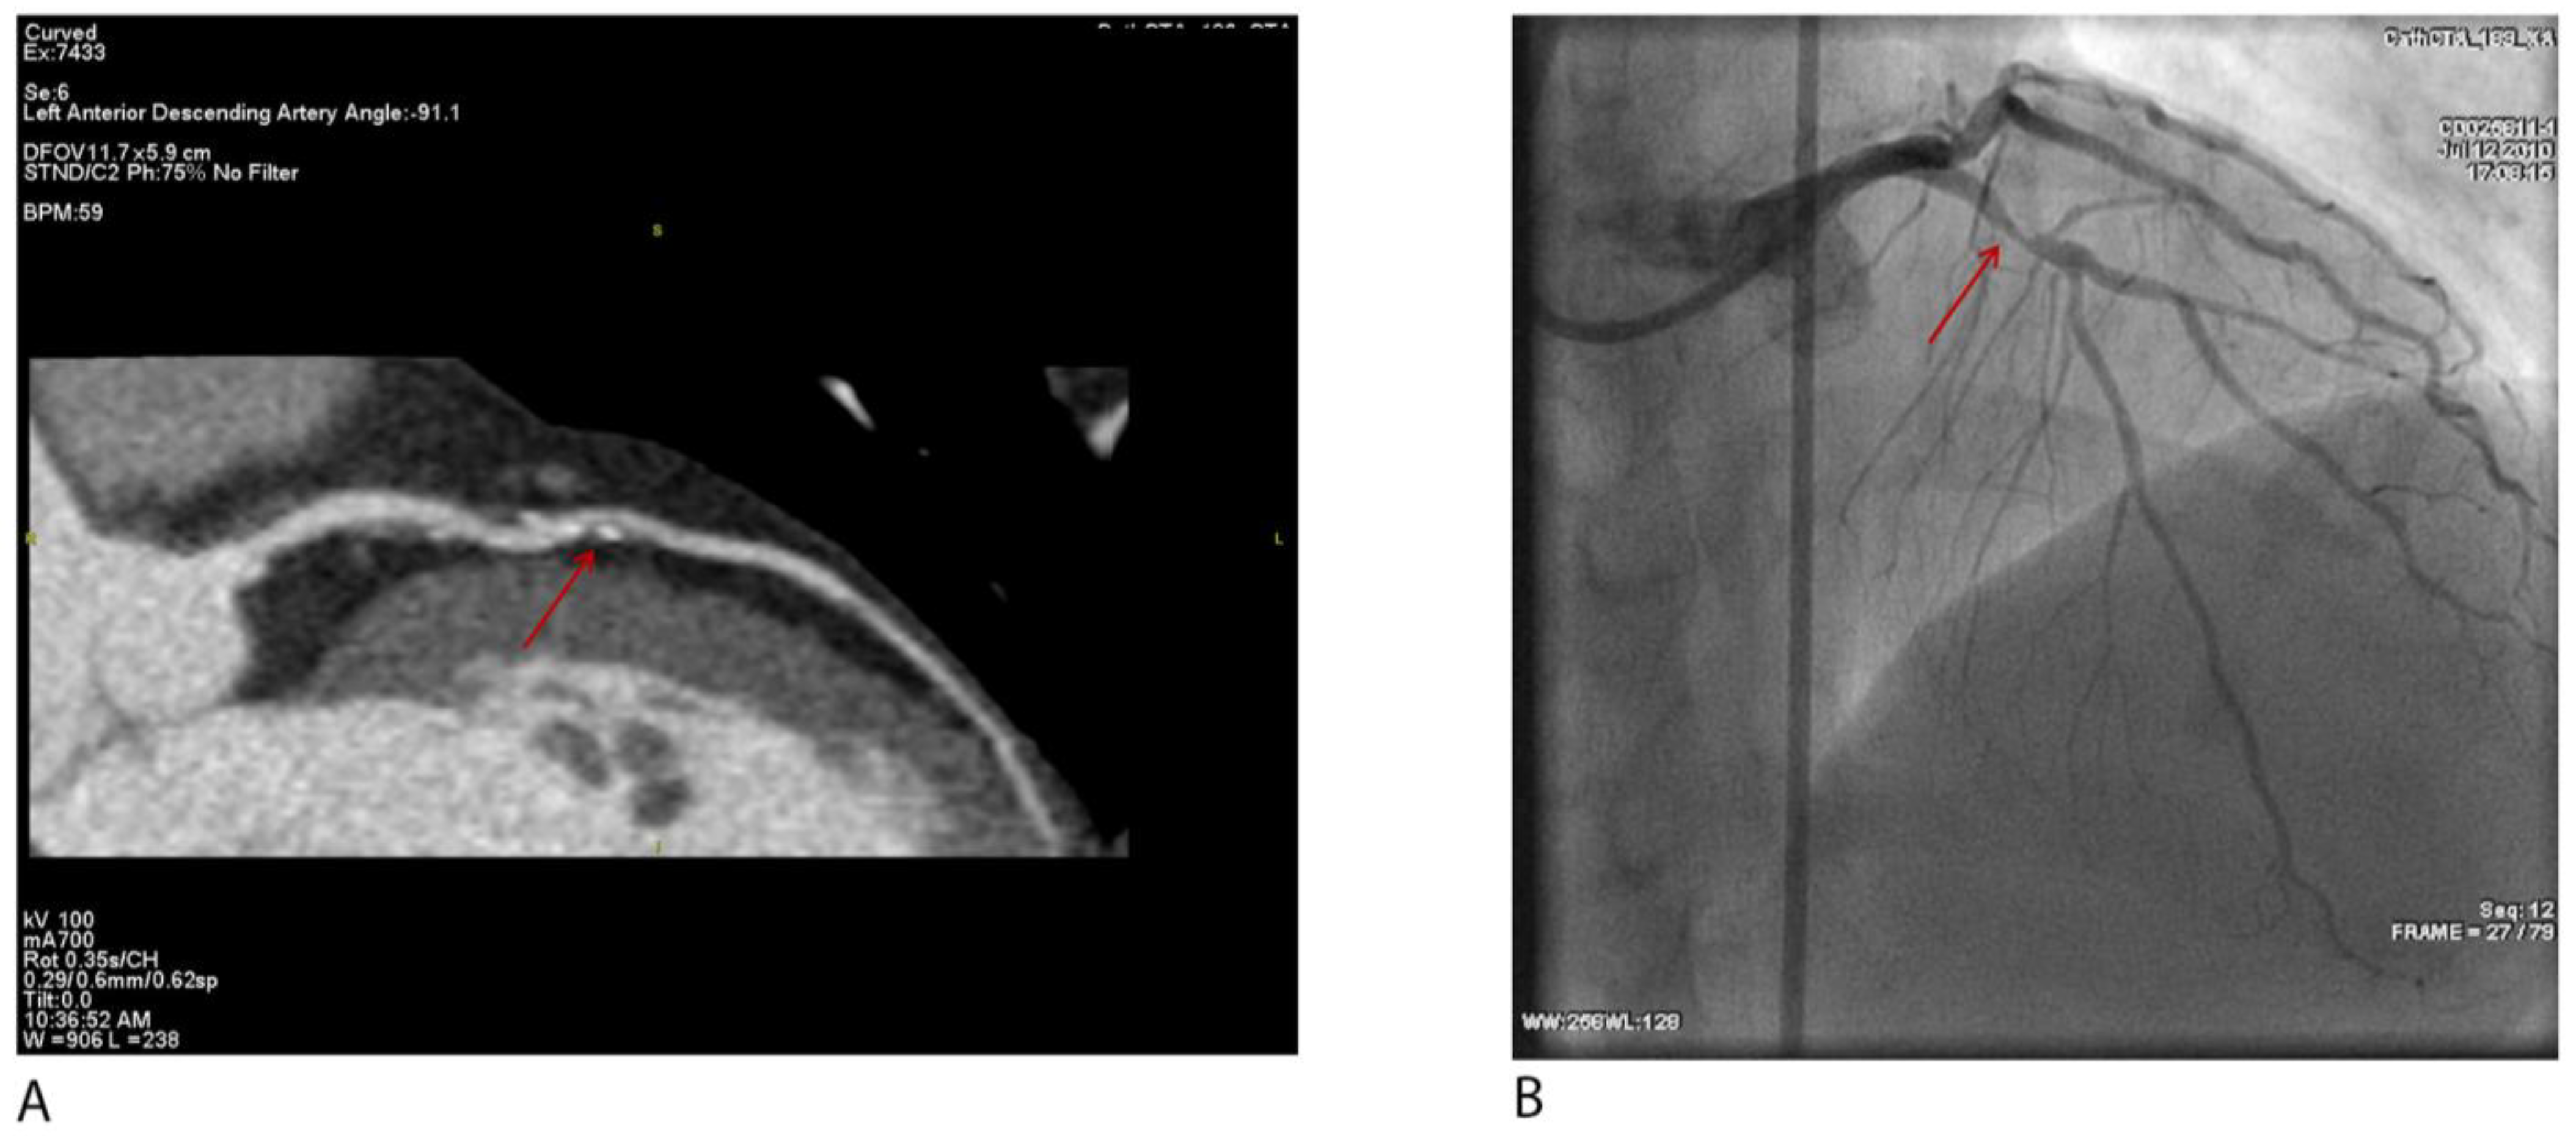

Figure 5A–C demonstrate anomalous LCx anatomy with significant stenosis and corresponding CT-FFR values, underscoring the added value of physiology-based interpretation for guiding therapy.

Figure 5. (A) Volume-rendered CCTA shows the left circumflex artery (LCx) originating from the proximal right coronary artery (RCA) and coursing retro-orbitally toward the left atrioventricular groove (arrow). (B) Curved-planar reconstruction depicts a severe (>70%) mixed-plaque stenosis in the proximal anomalous LCx (arrow); the ostial segment is normal in caliber. (C) CT-derived fractional flow reserve (CT-FFR) demonstrates preserved values (≥0.80) proximal to the area of stenosis, followed by a drop to <0.80 across the stenosis, indicating physiologic significance.